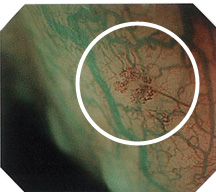

胃カメラ・大腸カメラともに、高画質なハイビジョンシステムによるクリアで高精細な観察が可能で、特殊光(NBI)により、微細な血管模様の変化をとらえ「がん」や「前がん病変」を早いうちに発見しやすくなります。

通常光

特殊光(NBI)